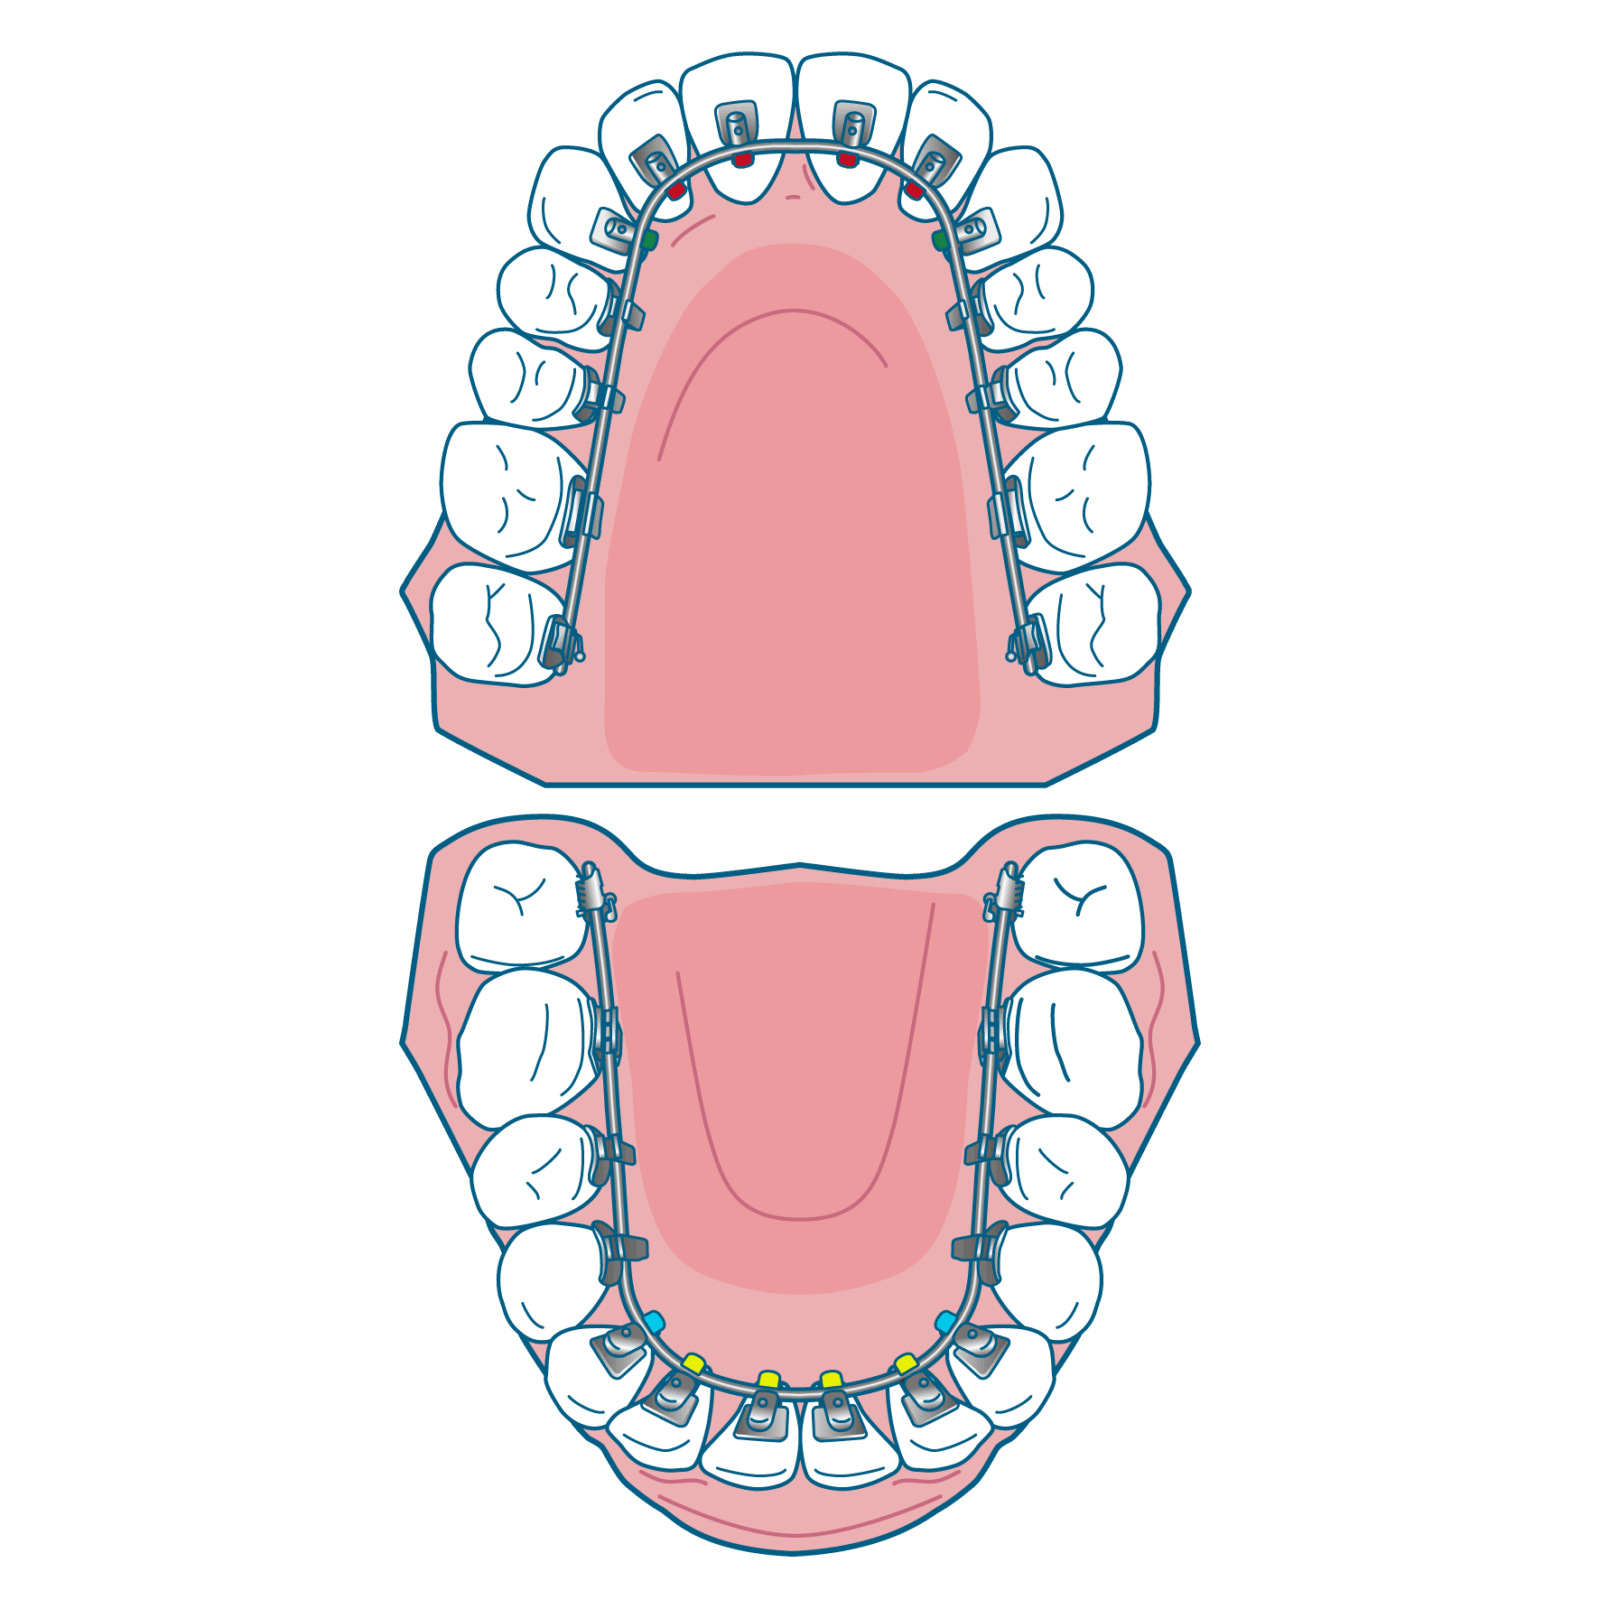

大人の矯正は「いつでも始められる」

大人の矯正はあごの成長が止まっているため、矯正治療だけで骨格自体を動かすことはできません。その代わり、歯の移動計画をより精密に立てられ、見た目だけでなくかみ合わせや歯の健康も長く保つことができます。最近は20代〜50代の方まで、幅広い年齢層の方が矯正治療をはじめています。

「社会人だから見た目が気になる」という方には、透明で目立ちにくく取り外しが可能なマウスピース矯正や歯の裏側に装置をつけるリンガル矯正などの治療方法も選ぶことができます。歯や歯ぐきの状態が良ければ、何歳からでも矯正治療は可能です。